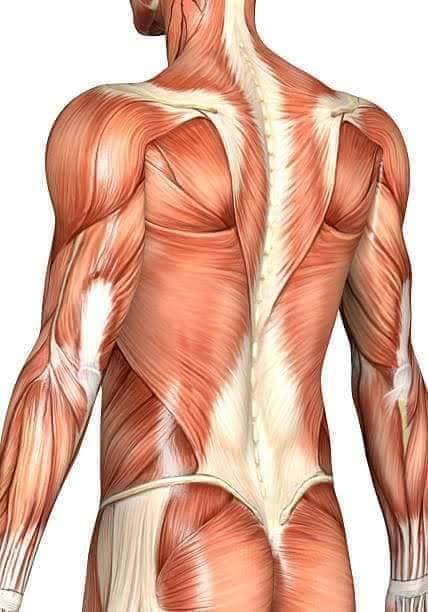

Спинні м'язи

Спинні м'язи виконують функції підтримки хребта, а також дозволяють здійснювати рухи тулуба.

Поверхневі спинні м'язи

М'язи, що піднімають лопатку: Трапецієподібний м'яз: великий м'яз, що покриває верхню частину спини. Його функція - підтримка і рух лопаток, а також забезпечення стабільності хребта.

М'язи, що ведуть лопатку до хребта: Широкий м'яз спини: великий м'яз, що розташований в нижній частині спини. Він відповідає за рухи плечей і лопаток, а також за розширення верхньої частини тулуба.

Глибинні спинні м'язи

М'язи, що забезпечують стабільність хребта: М'язи, що розташовані між хребцями: включають мускулатуру, яка забезпечує стабільність і підтримку хребта, а також дозволяє здійснювати рухи хребта.

М'язи, що здійснюють ротацію та нахили

М'язи, що забезпечують ротацію хребта: Ротаційні м'язи: допомагають у здійсненні обертальних рухів тулуба, а також у підтримці рівноваги і стабільності хребта.